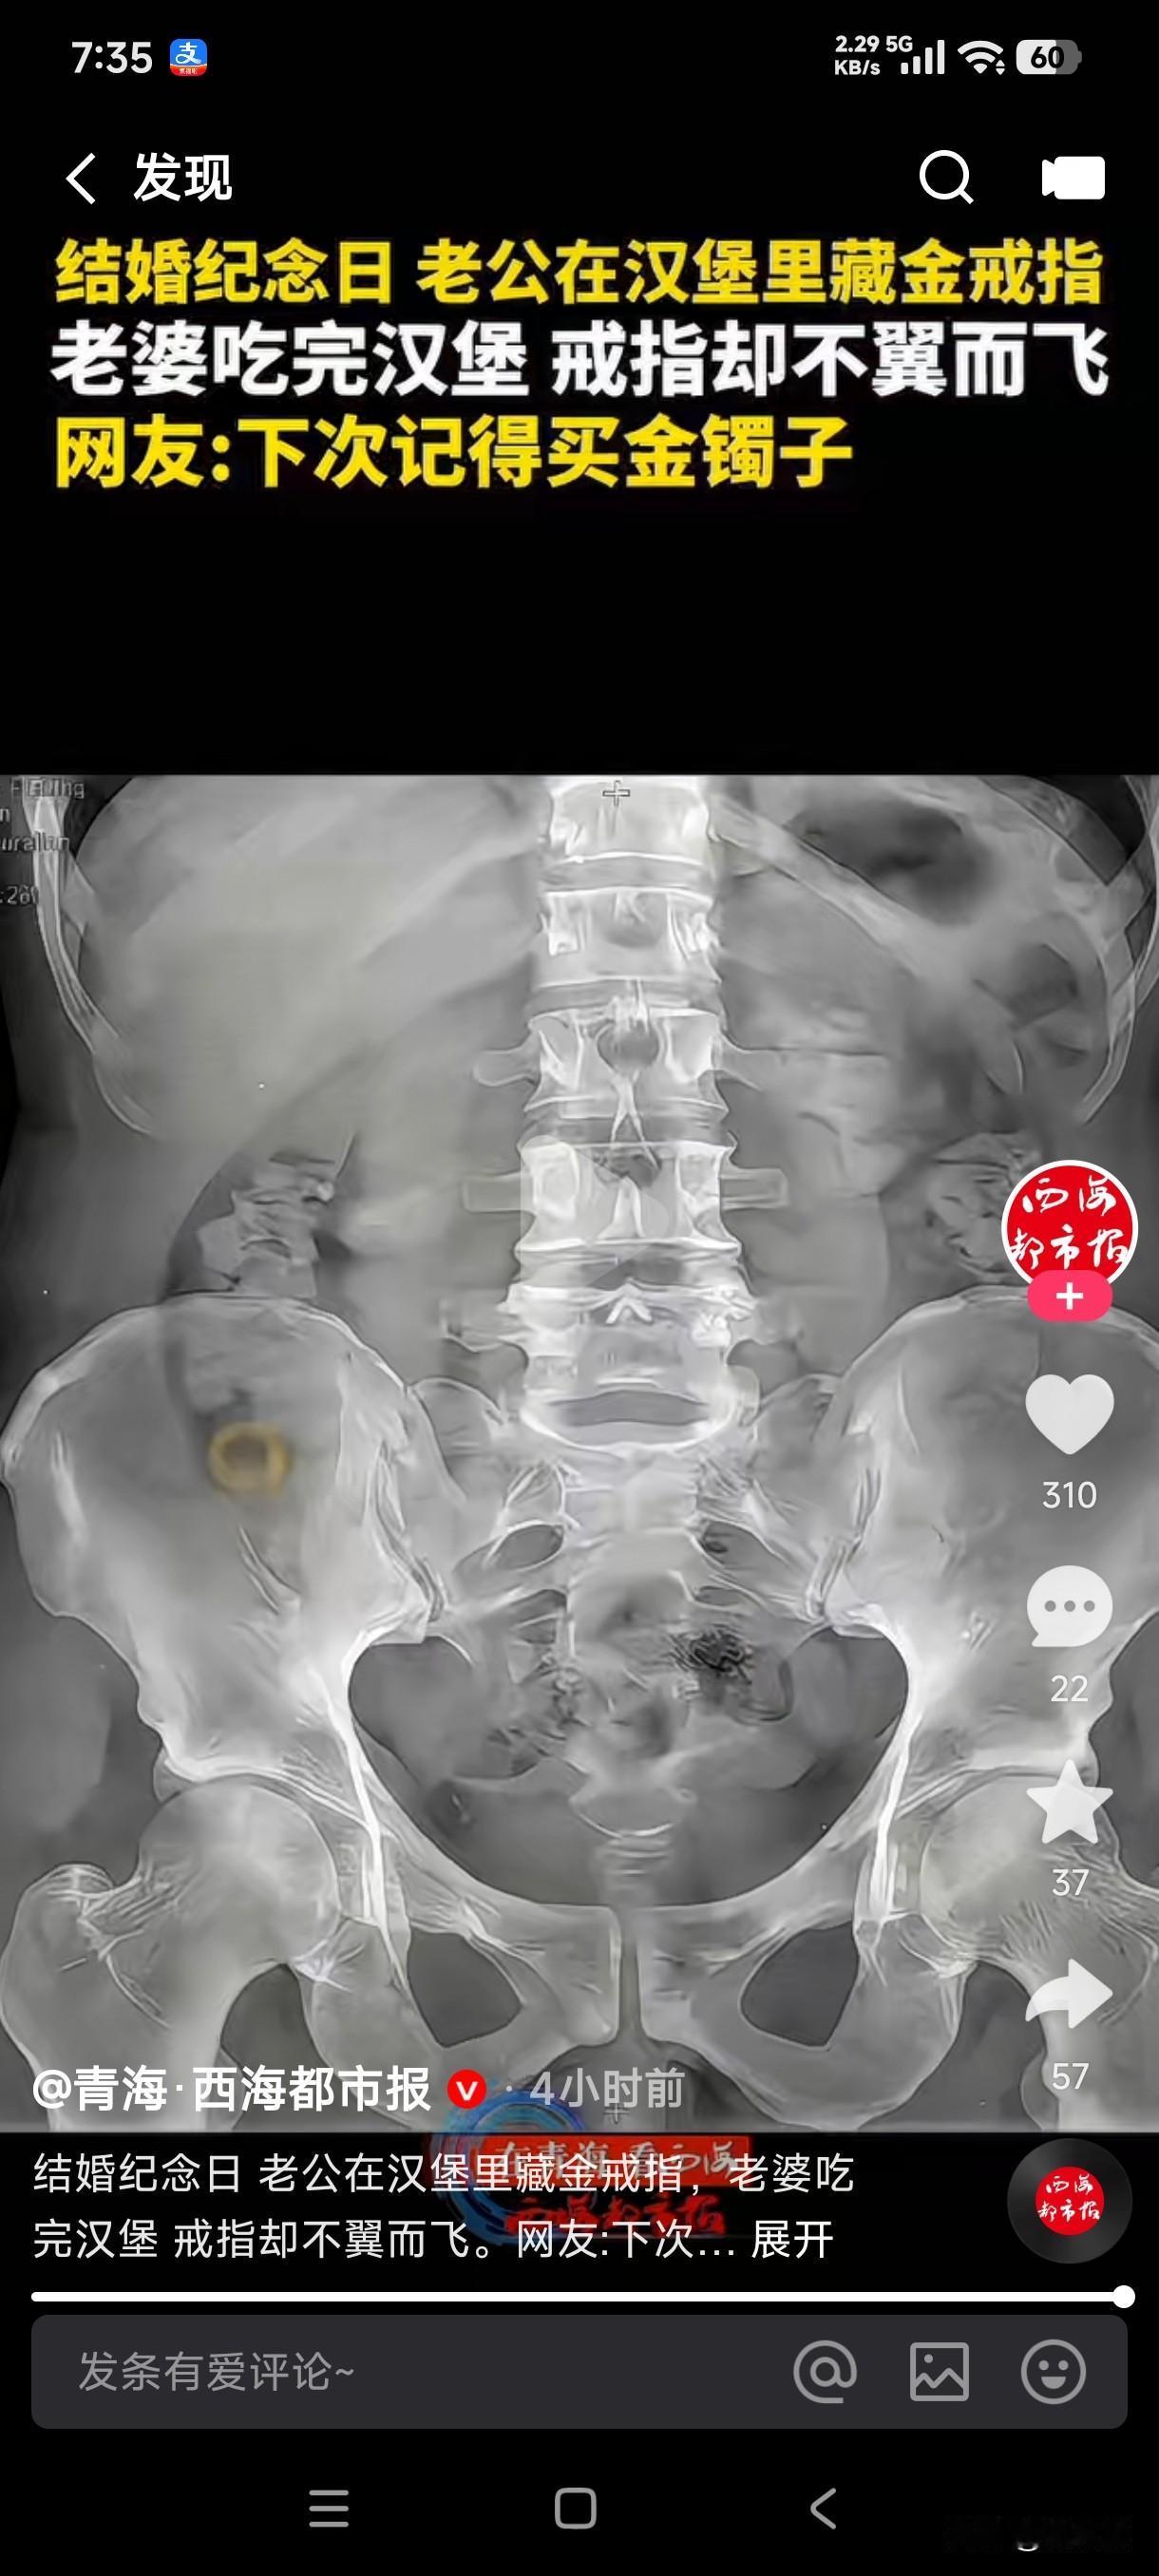

结婚纪念日老公在汉堡里面藏金戒指,老婆吃完汉堡戒指却不翼而飞了,最后上医院检查后发现戒指在老婆的胃里。 这女子吃东西从来不嚼吗?那么大一个汉堡她全程吃完居然没有发现金戒指的存在,这是她专心吃了汉堡了,还是她忘了结婚纪念日了,老公坐在旁边还等着她发现惊喜呢?直到她吃的一干二净都没有发现戒指的影子,老公还掰开她的嘴巴在嘴里找,最后居然进了她的肚子,这制造惊喜突然变成制造惊吓,最后还得去医院检查,这结婚纪念日是不是过的太有意义了? 这男子下次结婚纪念日肯定得买金镯子,还是按照上次的操作藏在汉堡里面的老婆在指定吃不到肚子里去了,这吃进肚子里的金戒指是做手术取出来?还是等她上厕所给拉出来?这以后戴在手上是不是都会有屎的阴影存在?